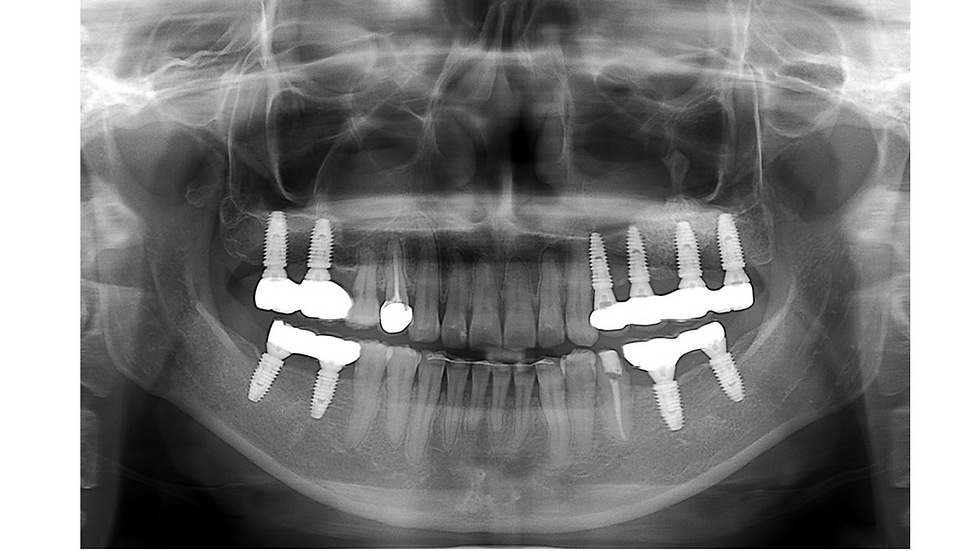

Panoramic x-ray (5 year follow-up).

Periapical x-ray after 5 years. Minimal bone loss around implants is observed.